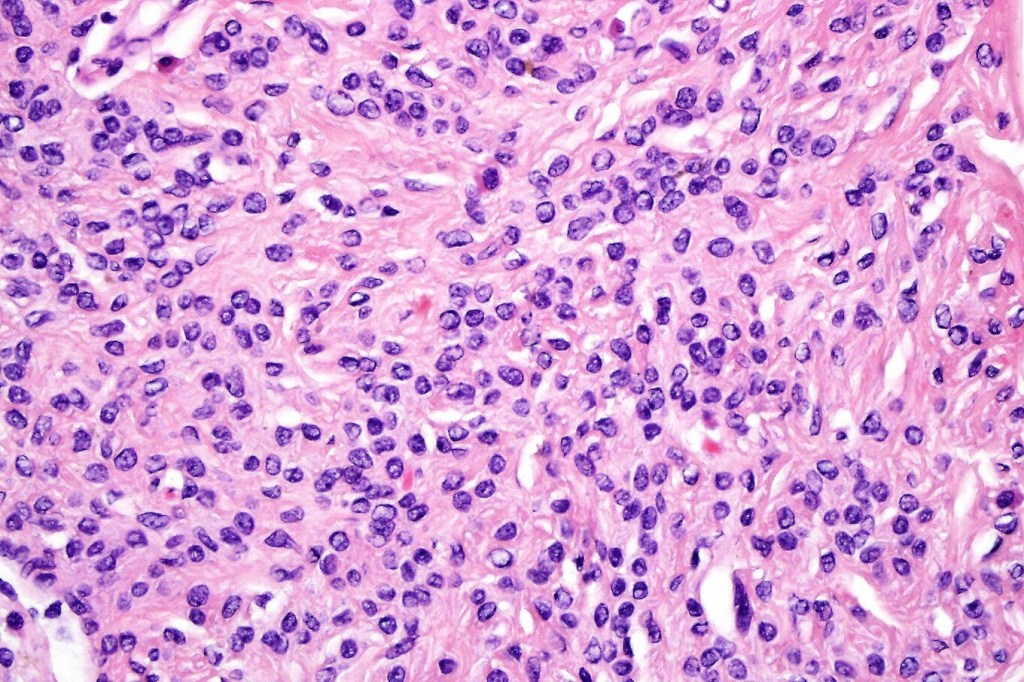

•It is hypercellular and most often composed of epithelioid cells showing little pleomorphism & only occasional mitoses

•Nuleoli are small

•Intracytoplasmic pseudo-inclusions

•The constituent cells are generally larger than the adjacent nevus cells

•Some examples show more marked pleomorphism with prominent nucleoli and increased mitotic activity but abnormal mitoses are not a feature. These are not associated with any sinister biological potential

•Spindle cell, small blue cell, blue nevus-like features, Spitzoid & proliferative nodules with mesenchymal differentiation (myofibroblastic, chondroid & osteoid) can be seen